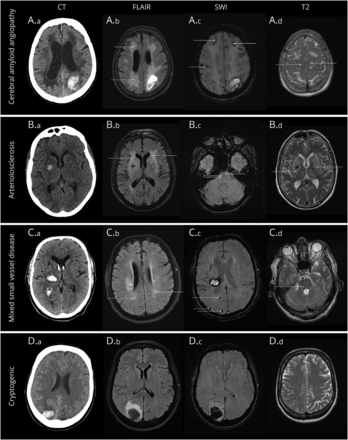

人口统计学和临床数据提取的全电子openMEDocs医院信息系统,已自1999年以来,用于大行政区。由一个训练有素的核磁共振扫描被评为神经与血管的专家(S.F.H.)额外审查的不确定性的高级神经与血管的专家(T.G.或D.J.W.)。核磁共振成像协议包括至少1 blood-sensitive序列(T2 * gradient-echo或susceptibility-weighted成像),T2加权fluid-attenuated反转恢复,T2加权和diffusion-weighted图像。包含在这项研究中,至少1诊断质量blood-sensitive序列和至少1 t2加权序列必须是可用的。根据我们调查血肿位置脑出血解剖评级工具(图表)13和trichotomized叶的,深(包括脑干)和小脑。在不确定的情况下,我们假定震中的位置确定的轴向片最大的直径我未受影响,并与相应的解剖学的半球13并进一步用CT、后续成像,或两者区分血肿位置。我们评估了血肿大小、伴随的蛛网膜下腔和脑室出血,皮质表面铁尘肺的存在和严重性(定义为传播如果影响> 3沟),14沉默的颅内出血或老旧的证据领土缺血性梗塞,和圣言会根据标记标准报告血管神经影像学变化(努力)标准。9脑的严重程度和分布microbleeds被评为Microbleed解剖评定量表,15室和深度研究负责人根据法泽卡斯规模,16和扩大血管周的空间根据分制评分进行验证17在椎体semiovale和基底神经节。负责人根据法泽卡斯范围被定义为严重的2 - 3在3 - 4的得分和ePVS严重视觉评定量表。我病因分为创新艺人经纪公司时的标准可能的创新艺人经纪公司根据最近发表的波士顿2.0版标准18已经实现。我们分类引起小动脉硬化患者non-lobar我和相应的适当的圣言的迹象(至少1缝隙,中度或严重的负责人,microbleeds深处,或严重扩大基底神经节血管周的空间),没有任何证据,大叶性microbleeds或叶的我。患者重要的圣言的迹象不合适的创新艺人经纪公司或小动脉硬化的标准(例如,混合了大叶性和深度计算的迹象被分组为混合计算。病人没有任何MRI可见圣言的迹象(没有microbleeds,可见,中度/重度的负责人,也严重扩大血管周的空格)被定义为不明原因引起的。4组的例子所示图2。

绿色箭头表示不同功能的脑小血管疾病(计算)。上面一行:大叶性患者枕我由于可能的脑淀粉样血管病(一位)。MRI显示广泛的融合性的白质hyperintensities (A.b),传播皮质表面铁尘肺,无数大叶性microbleeds(交流),和严重扩大血管周的空间在中枢semiovale(公元)。这个病人有反复大叶性指数我。我2个月后第二行:患者深我在基底神经节(本科)由于小动脉硬化。MRI显示汇合的白质hyperintensities(反方向),深microbleeds(公元前)和严重扩大血管周的空间的基底神经节(B.d)。第三行:病人丘脑我(一个)和混合计算功能。MRI描绘了早期汇合的白质hyperintensities (C.b),可见(C。b, C.d),和几个大叶性microbleeds (C。c,进一步深microbleeds没有显示)。底下一行:患者不明原因引起的大叶性枕我(地方检察官)没有任何迹象的圣言(除了一些点状的白质hyperintensities D.b)。详细的检查包括重复MRI和数字减血管病排除结构或macrovascular原因。